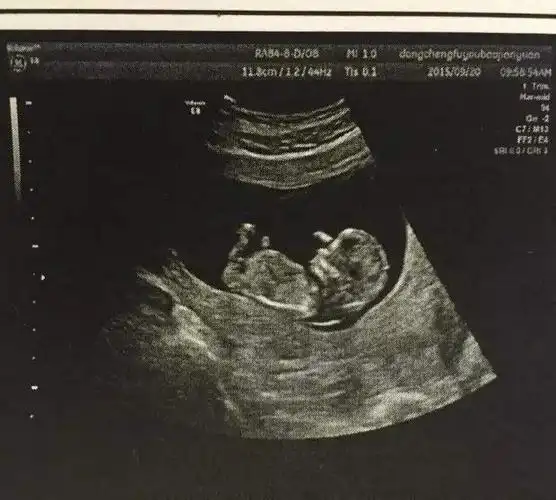

想要小棉袄的孕妈,b超单上经常出现这3种情况,美梦可能要成真了_宝宝

b超单上的3组"数据",或许是胎儿在告知准爸妈自己是个男宝_进行_宝宝

b超大排畸能看胎儿性别吗?